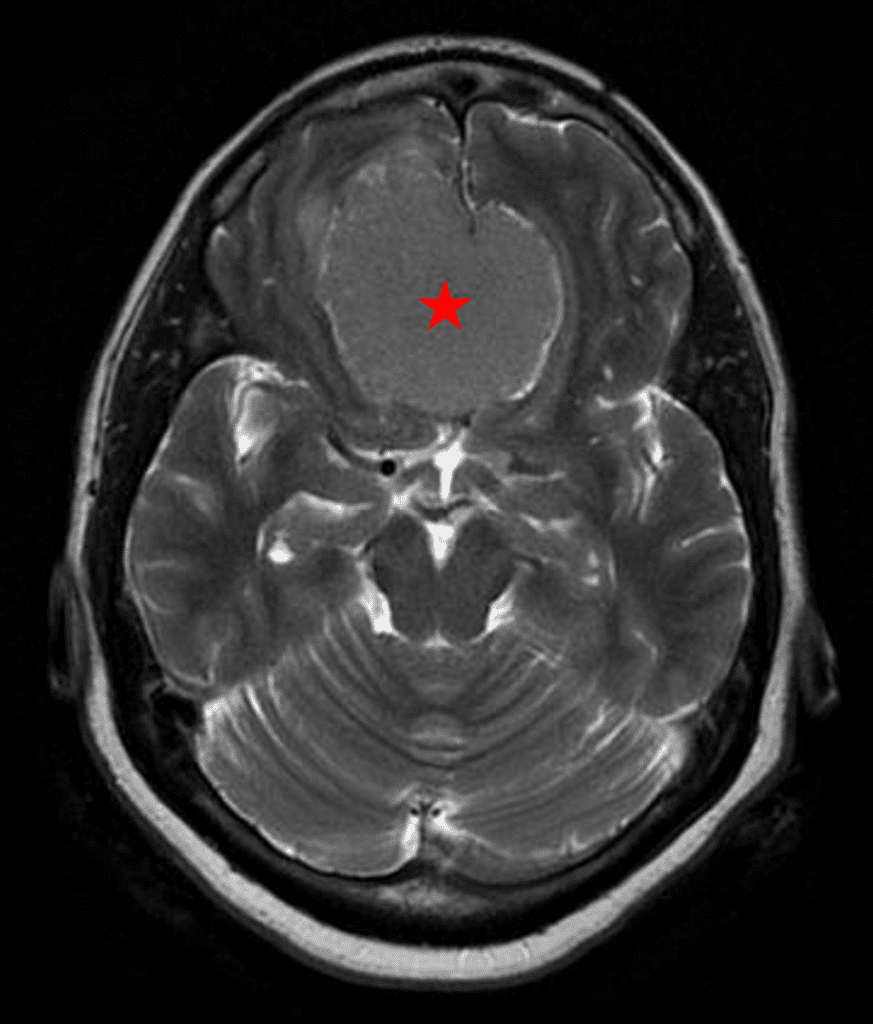

She was started on high-dose steroid and antiseizure prophylactic medicine. Surgical intervention was offered for mass effect, symptomatic relief, neurologic preservation, and histopathologic diagnosis. Dr. Gaudin performed a bifrontal craniotomy with complete resection of neoplasm through an interhemispheric and subfrontal approach. Postoperative imaging demonstrated a gross total resection without residual tumor and resolution of mass effect (Figure 1b and 2b). Intraoperative pathology was consistent with meningioma, WHO grade 1. She recovered very well, and was discharged home on postoperative day 3. On her follow-up outpatient visit, her preoperative symptoms had fully resolved, and her olfactory sense was maintained.

Figure 2a – Preoperative MRI demonstrating an extra-axial lesion with surrounding vasogenic edema and mass effect on the frontal lobes.

Figure 2b – Postoperative MRI demonstrating resolution of mass effect.